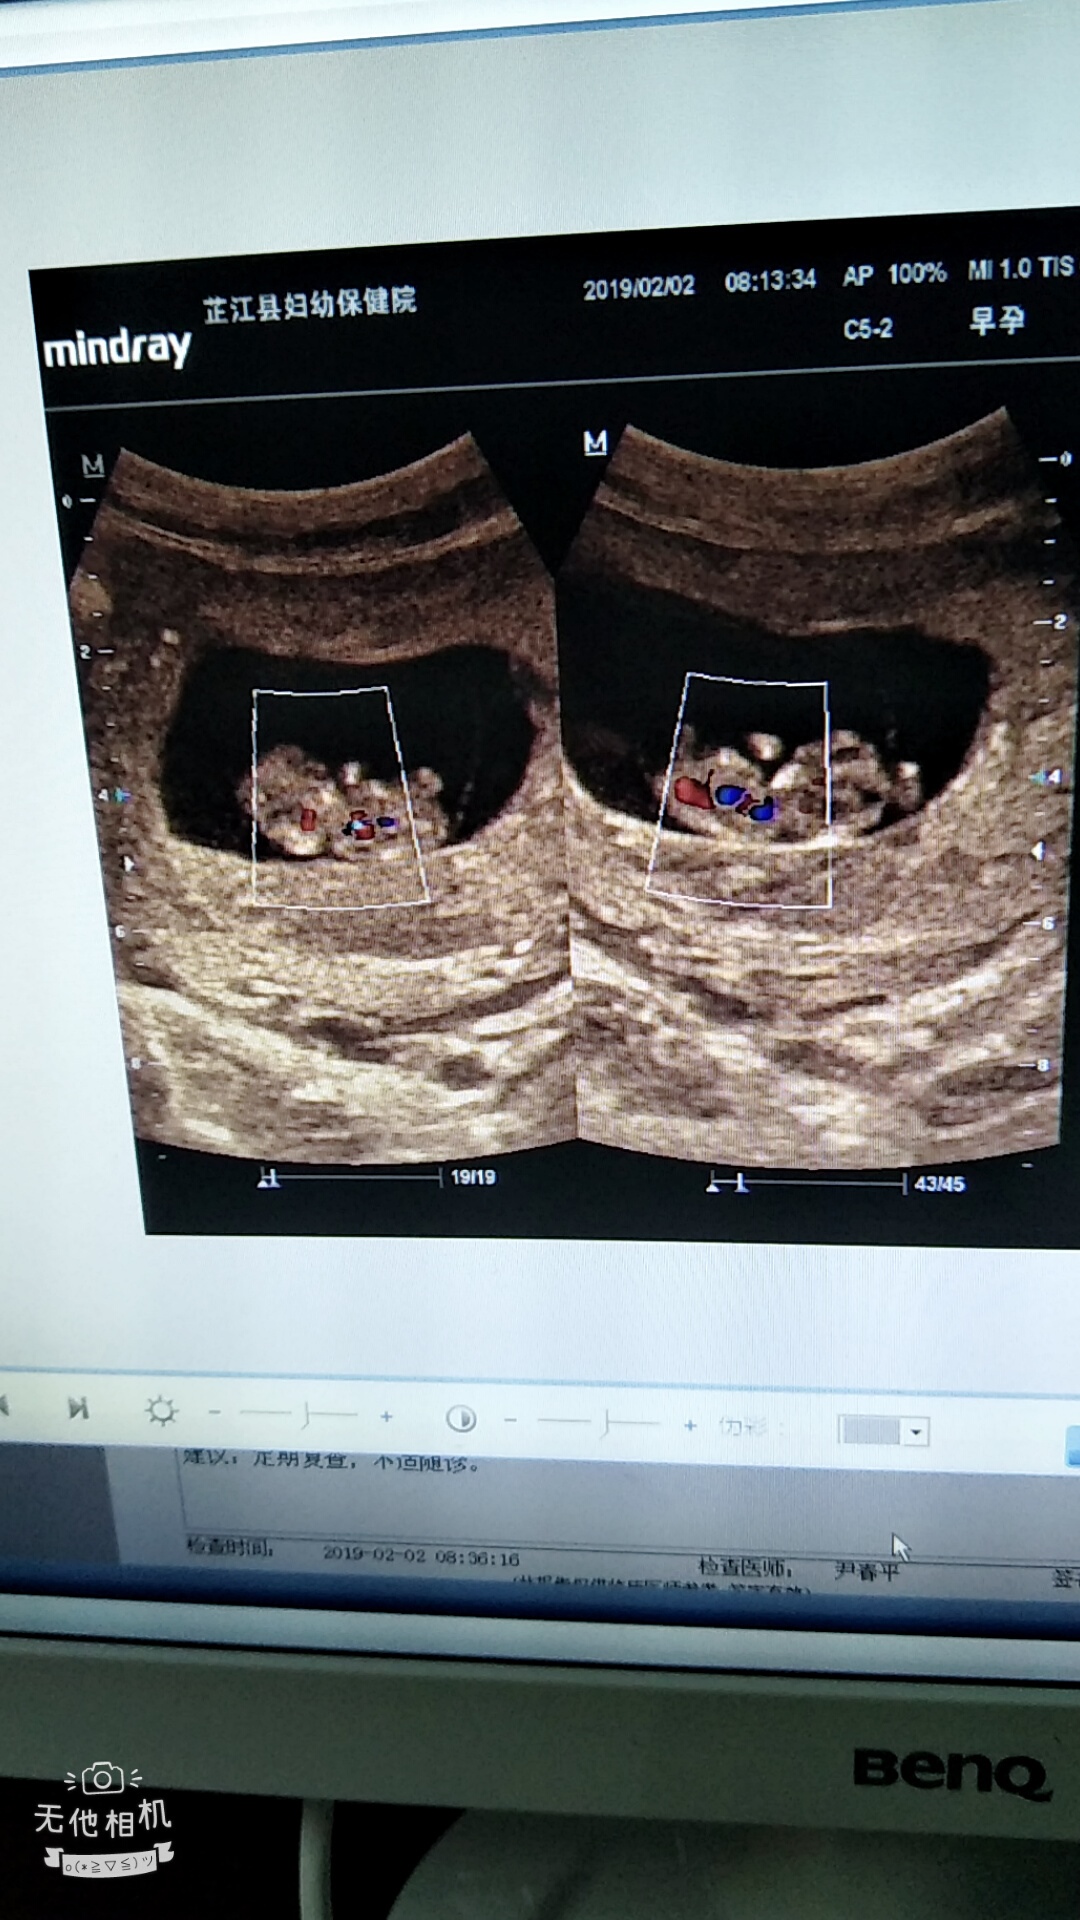

产前检查 B超